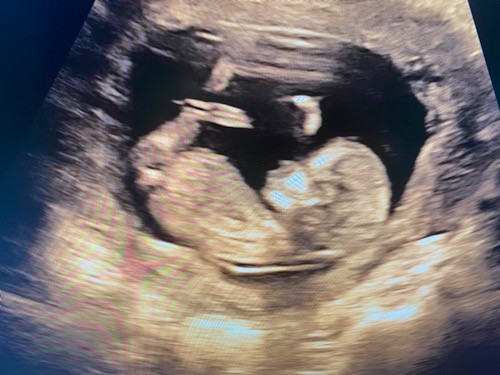

Ktoś potrafi z tych zdjęć określić płeć ? :)

Ps. Lekarz powiedział ze jakby miał obstawiać to dziewczynka ale z tego „ siusiaka „ może być jeszcze chłopak 🙈

• 15D633E6-8C00-4308-9859-67A5D4C60E1C.jpeg

15D633E6-8C00-4308-9859-67A5D4C60E1C.jpeg

53,8 KB · Wyświetleń: 93